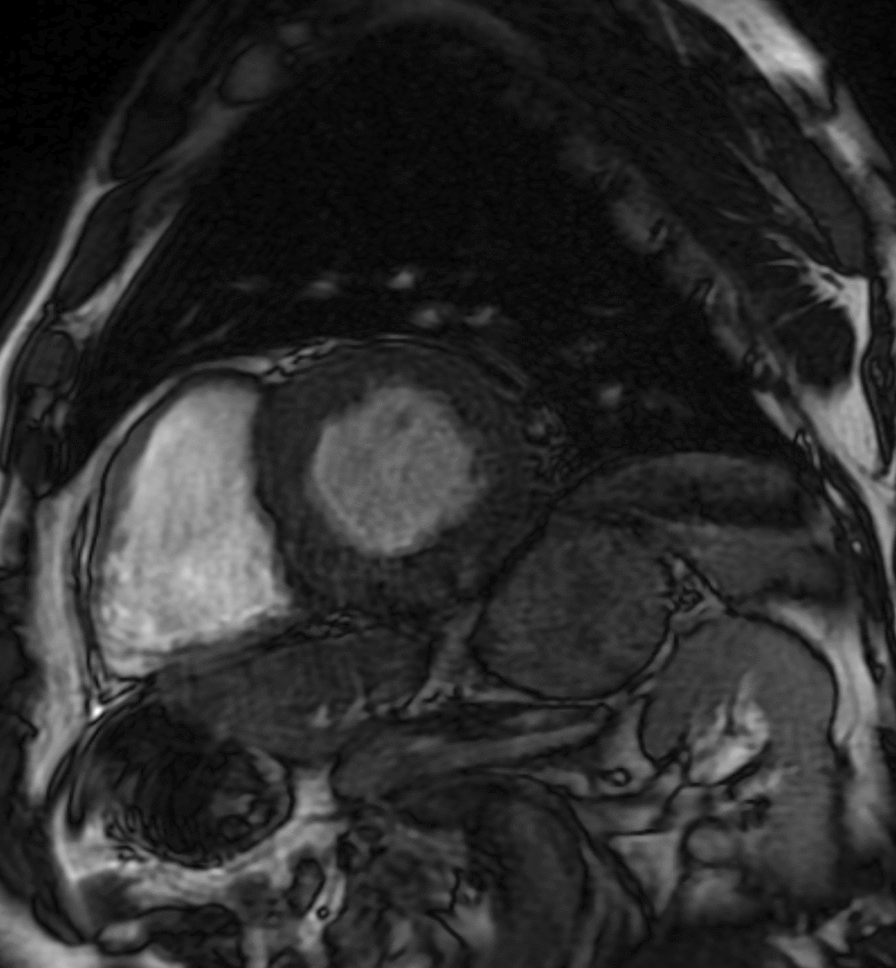

Case presentation: A 66-year-old Mexican male patient with a family history significant for hereditary amyloidosis presented with intermittent chest pain, shortness of breath, and neurological symptoms. An echocardiogram done at an outside hospital showed an ejection fraction of 55-60% with grade 2 diastolic dysfunction. A technetium pyrophosphate scan was used to make the diagnosis of transthyretin amyloidosis, and genetic testing showed that the patient was heterozygous for p.G67A (also known as c.2000G > C) pathogenic mutation in the transthyretin (TTR) gene. Due to these findings the patient was started on tafamidis free acid 61 mg daily and vutrisiran (Amvuttra) injections. He was also given vitamin A supplementation to prevent vutrisiran-associated vitamin A deficiency, which is a known side effect.